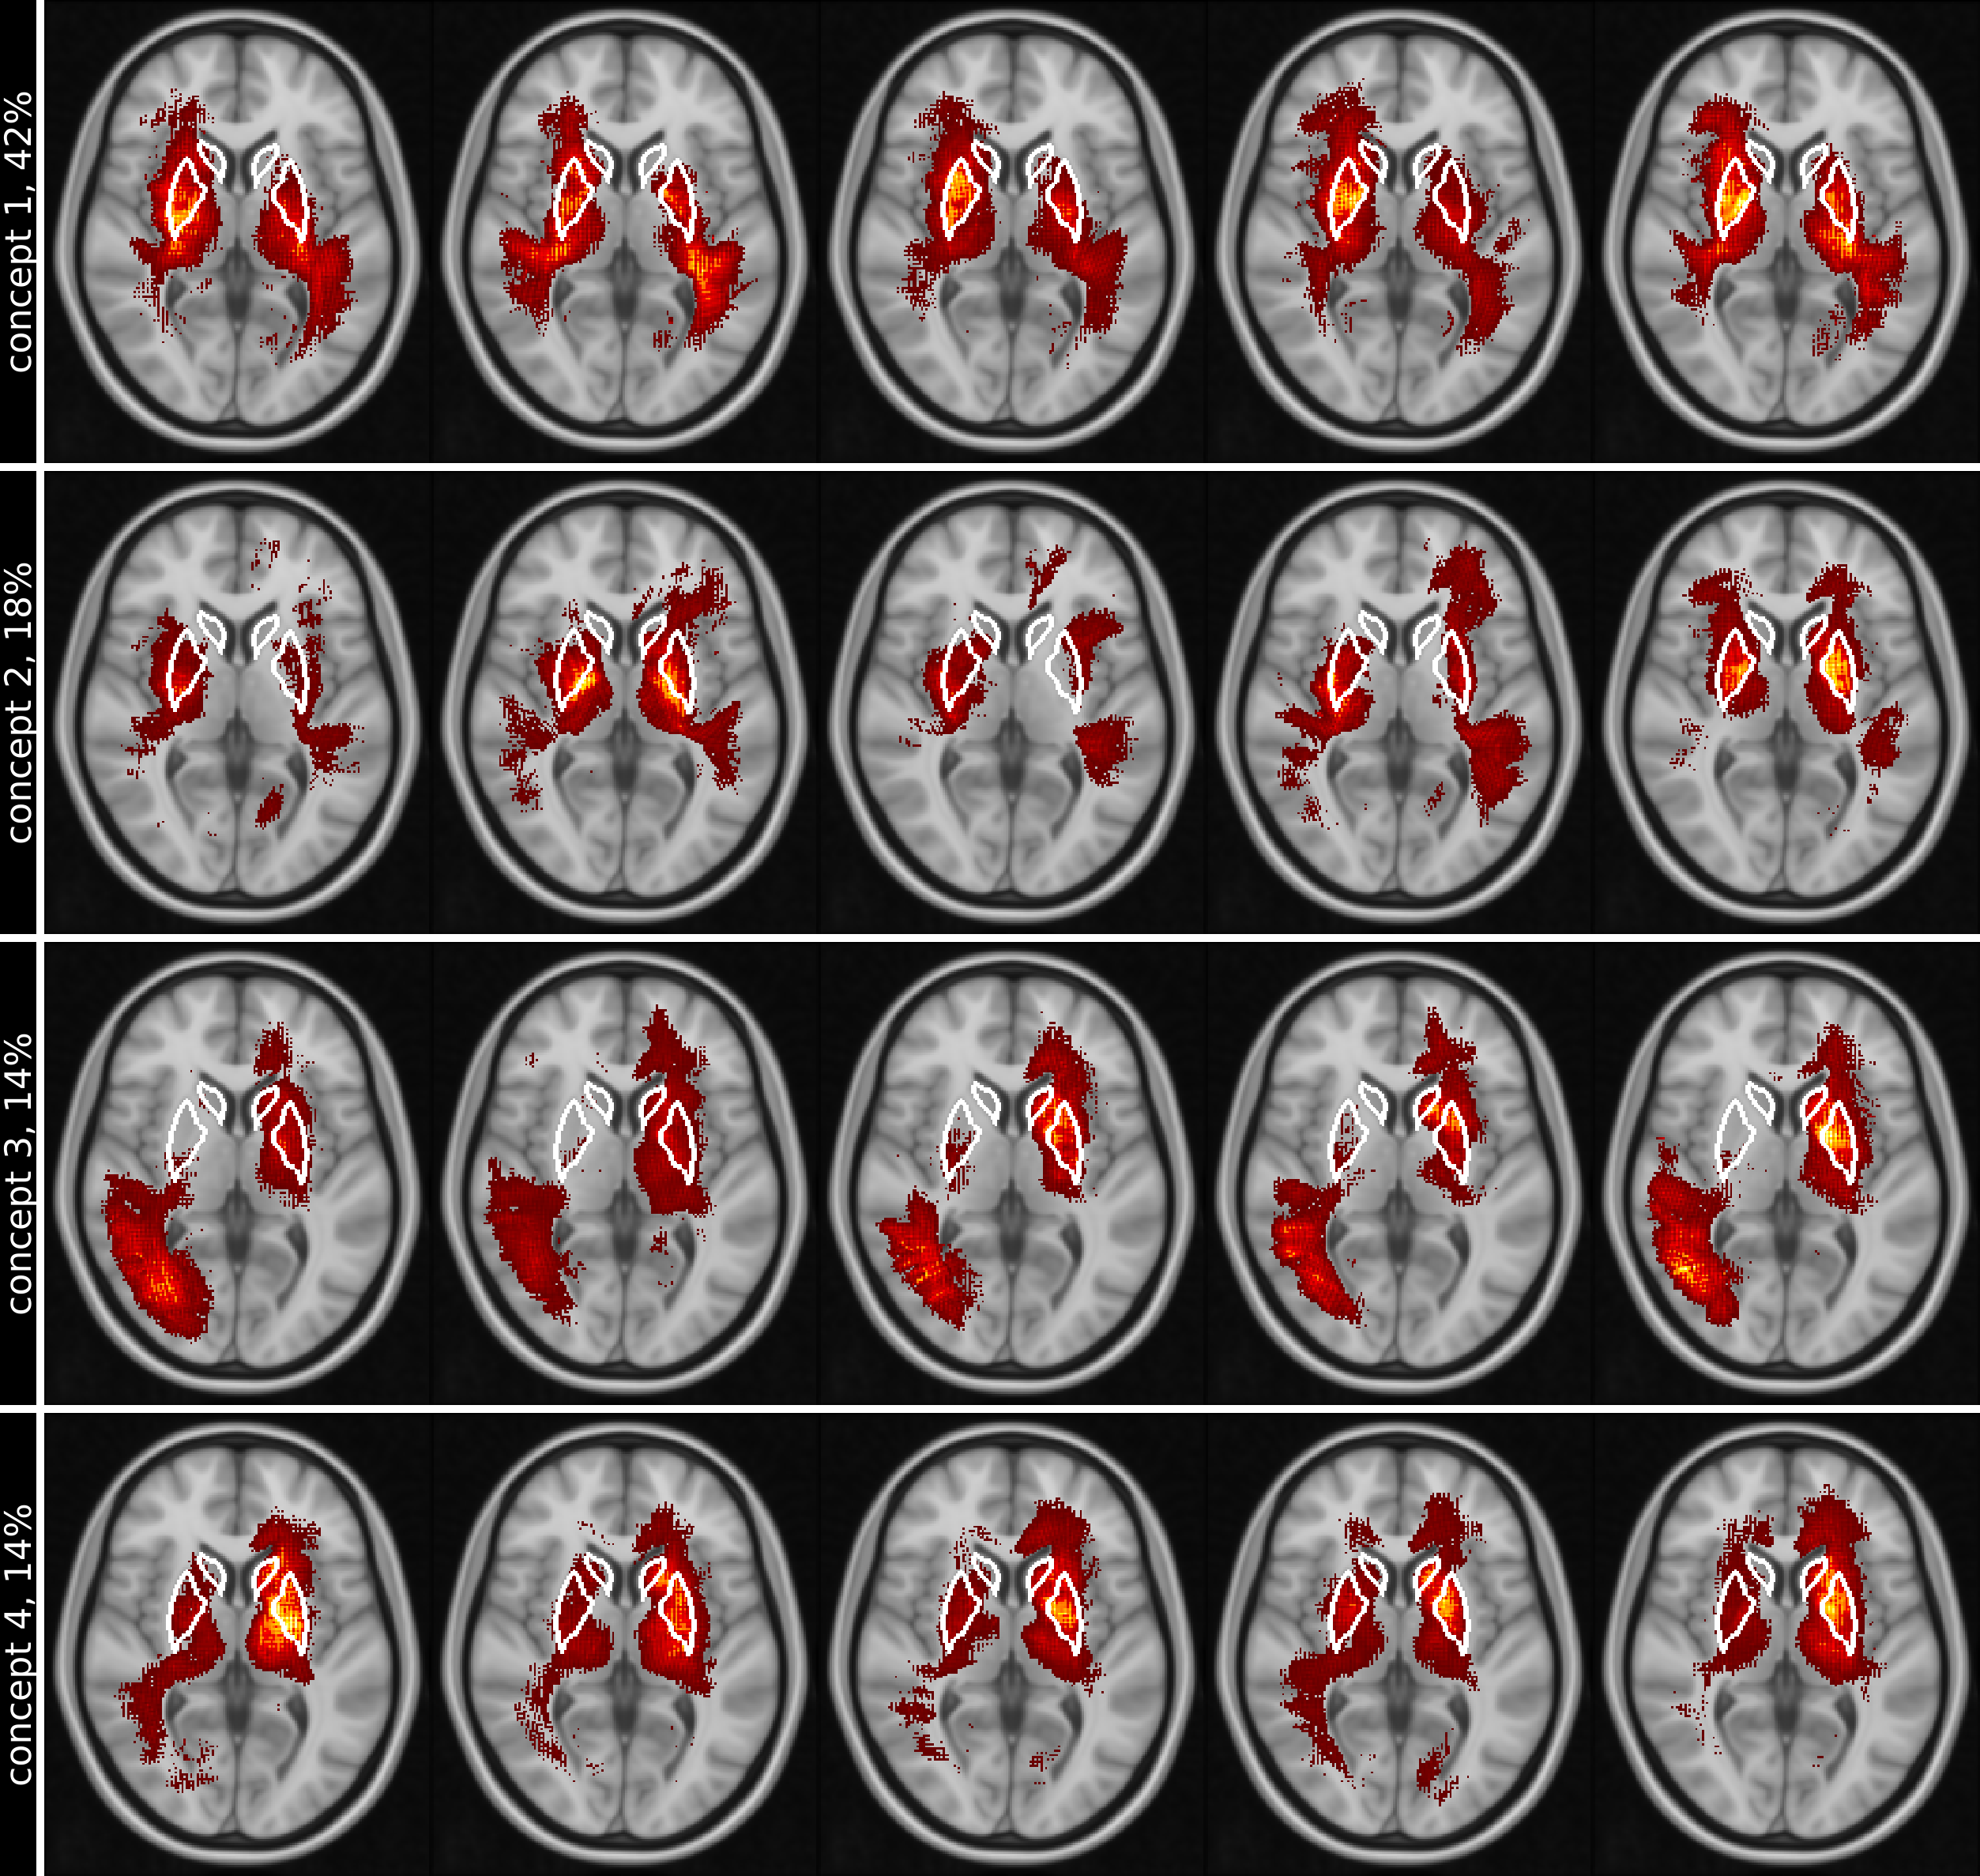

Figure  3 shows the five top ranked test images for each concept on the same transversal slice, while figures 4 and 5 show the mean concept maps for NC and AD on five transversal slices.

Refer to caption

Figure 3: Rows (1) to (4) show the 4 most important concepts, ranked by their relative importance (percentage next to name) for the classification results. Columns (1) to (5) show the 5 top ranked individual test images for each concept on the same transversal slice. Positive relevance, shown as red-yellow, highlight regions in concepts with higher attributions. White lines in slices outline the basal ganglia. Images are shown in standard-radiological view, causing the left and right side of the brain to be flipped.